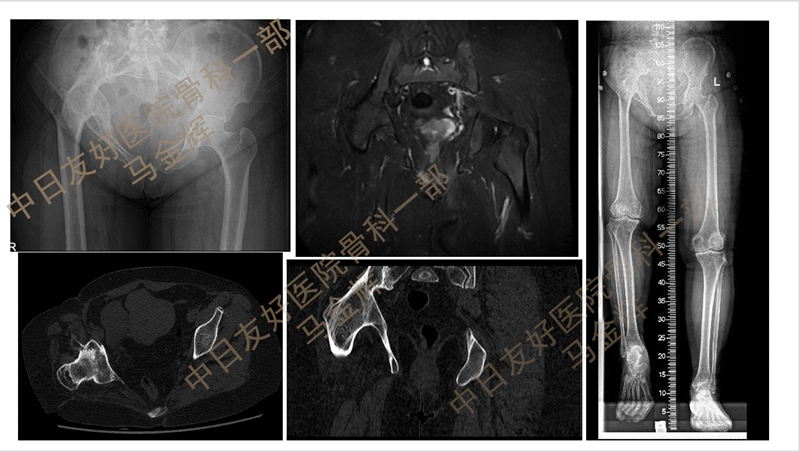

50岁中年女性,右髋关节跛行伴活动受限30余年,既往3岁时因右髋关节化脓性关节炎行反复清创、引流3次;

入院诊断:右髋关节化脓性关节炎后遗症、右髋关节强直,拟行右侧全髋关节置换术,行AI术前规划,顺利实施THA,术后患者恢复良好。